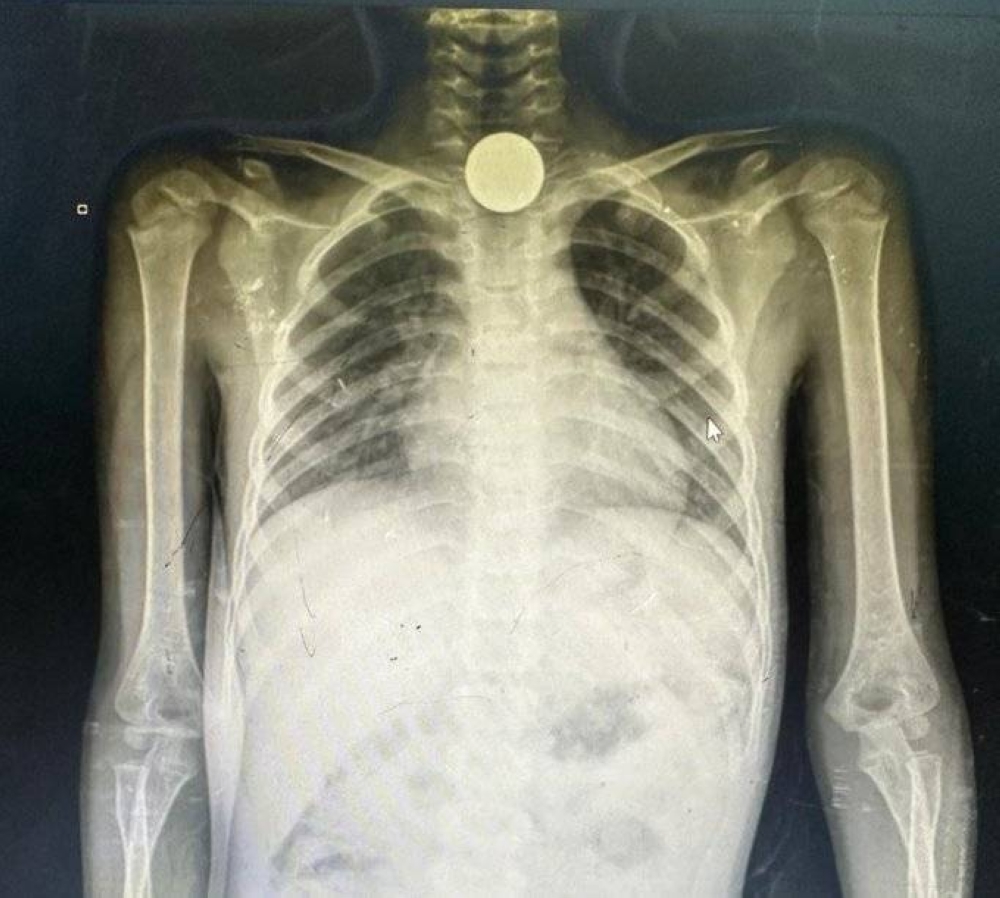

ففي حسابه على منصة “إكس”، أوضح الطبيب خالد الشموسي أن أحد الأطفال ابتلع قطعة معدنية افانحشرت في مريئه حيث عرض صورة شعاعية لصدر الفتاة الصغيرة التي عاينها معلقا بالقول: “أطفال غزة يأكلون العملات المعدنية والحصى والبطاريات الصغيرة من شدة الجوع.. الأمة العربية والإسلامية تتحمل وزرهم.. هذا إحداهم وعمرها 8 سنوات.. ابتلعت قطعة معدنية وانحشرت في مريئها”.